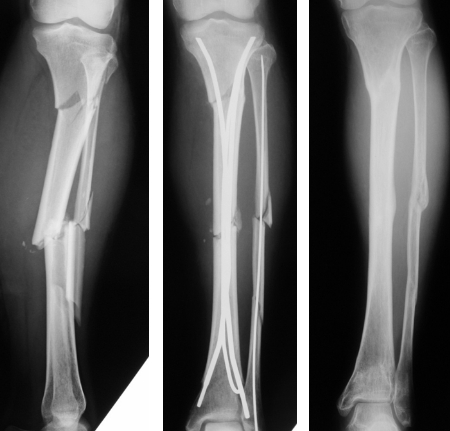

(1)脛骨骨折:下腿は軟部組織が菲薄で特に脛骨遠位は開放骨折になりやすい傾向にあります。Ender釘の挿入は比較的容易で挿入部位が4ヵ所あり、開放創を避けて挿入することができます。分節骨折に対してもよい適応があります(図6)。

(2)学童期の大腿骨/脛骨骨幹部骨折:治療の多くは非観血的治療ですが、転位を伴った場合には観血的治療が望ましい症例もあります(図7)。早期の復学を目指す手術方法として有効で術後早期に自動運動が可能であり、入院期間を短くし家族の負担も減らせます。Ender釘は骨端線を避けて挿入することが可能であり、長さや径も豊富です。

(3)既存インプラントがある下肢骨折:既存インプラントを避けて挿入することができれば有用です(図8)。

図6 脛骨分節骨折に対するEnder髄内釘固定術

図7 学童期の大腿骨骨幹部骨折に対するEnder髄内釘固定術

図8 プレートを避けてEnder髄内釘を挿入